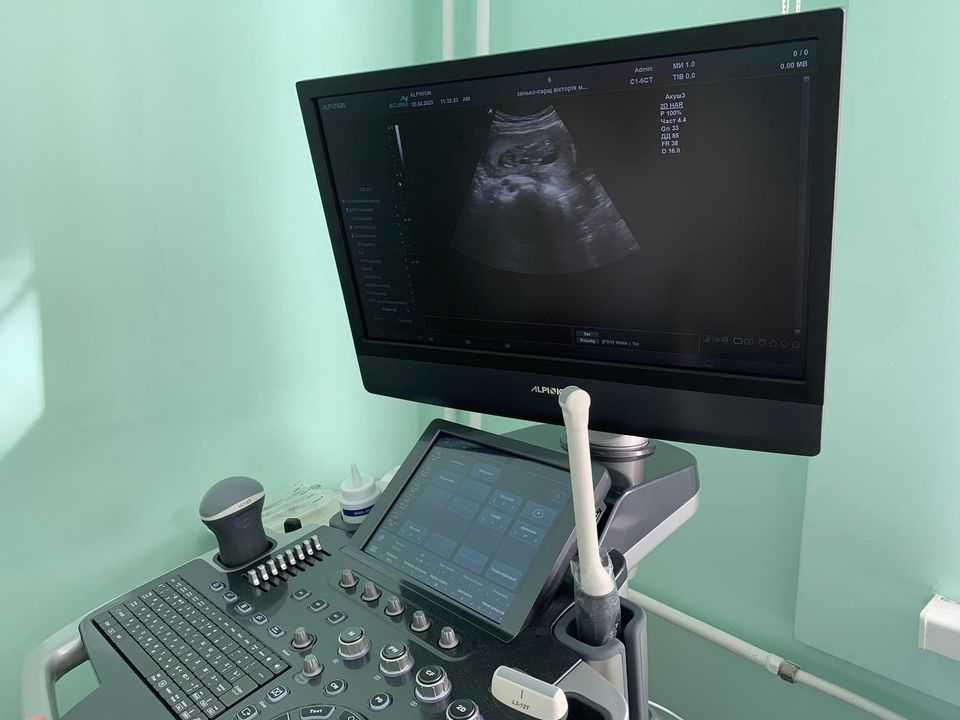

Соснівська міська лікарня отримала сучасний апарат ультразвукового обстеження ECUBE 8 виробництва Кореї, який придбано за кошти міського бюджету.

«Як тільки обладнання було змонтоване в кабінеті, ми одразу розпочали обстеження пацієнтів. Оскільки апаратура сучасна, багатофункціональна, то потрібен певний час для того, аби ознайомитись із можливостями апарату і приступити до повноцінної діагностики пацієнтів» - розповіла лікар-гінеколог Соснівської міської лікарні Людмила Ярович.

«За цей тиждень ми провели обстеження вагітних на 1, 2 та 3 триместрі, а також пацієнток з гінекологічними і навіть онкологічними паталогіями. Цей УЗД-апарат цінний для медиків Соснівської міської лікарні та мешканців громади насамперед тим, що має розширені можливості обстеження пацієнтів з різною паталогією і за різних показів.

Завдяки наявності шести датчиків, на цьому обладнанні можна проводити діагностику не лише гінекологічного призначення, а й робити кардіологічні та урологічні обстеження, дослідження судин, малих органів, грудної клітки, опорно-рухового апарату» - зауважила медик.